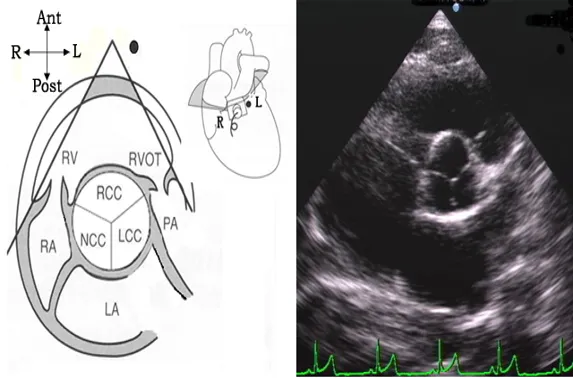

胸骨旁大动脉短轴切面

探头位置:探头置于胸骨左缘2、3肋间,在左心室长轴切面基础上探头顺钟向旋转90°或者是在大动脉短轴切面基础上心尖偏转法。

观察内容:

● 腔室大小:右室流出道、肺动脉。

● 瓣膜活动:主动脉瓣、肺动脉瓣。

● 结构的连续性:房间隔、室间隔、动脉导管。